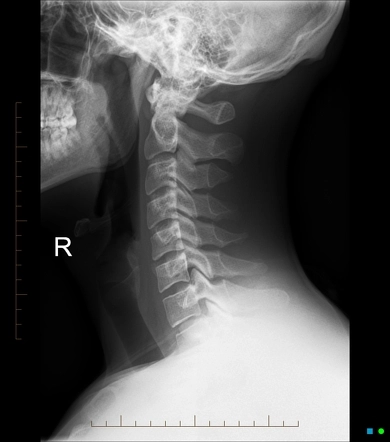

X-ray Cervical Lateral

X-Ray Cervical Spine Lateral view is an imaging test that aids in detecting cervical spine fractures, dislocations, bone lesions, and degenerative disorders. It helps visualize any neck and cervical spine abnormalities.